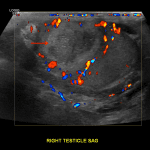

Indication: Right testicle pain and swelling

- Asymmetrically increased Doppler flow in the right testis and right epididymis

- Circumscribed, heterogeneous, hypoechoic lesion with hyperechoic internal reflectors measuring 2.4 x 2.3 x 1.6 cm in the right testis with a hyperechoic rim and lack of internal Doppler flow

- Small right hydrocele

Epididymo-orchitis with testicular abscess

Asymmetrically increased Doppler flow in the right testis and right epididymis, consistent with epididymo-orchitis.

Circumscribed, heterogeneous, hypoechoic lesion with hyperechoic internal reflectors measuring 2.4 x 2.3 x 1.6 cm in the right testis with a hyperechoic rim and lack of internal Doppler flow, concerning for a testicular abscess. However, a necrotic testicular neoplasm, segmental testicular infarct, or granulomatous disease could have a similar imaging appearance. Recommend followup imaging after treatment to ensure expected evolution of findings and to exclude neoplasm.

Small reactive right hydrocele.